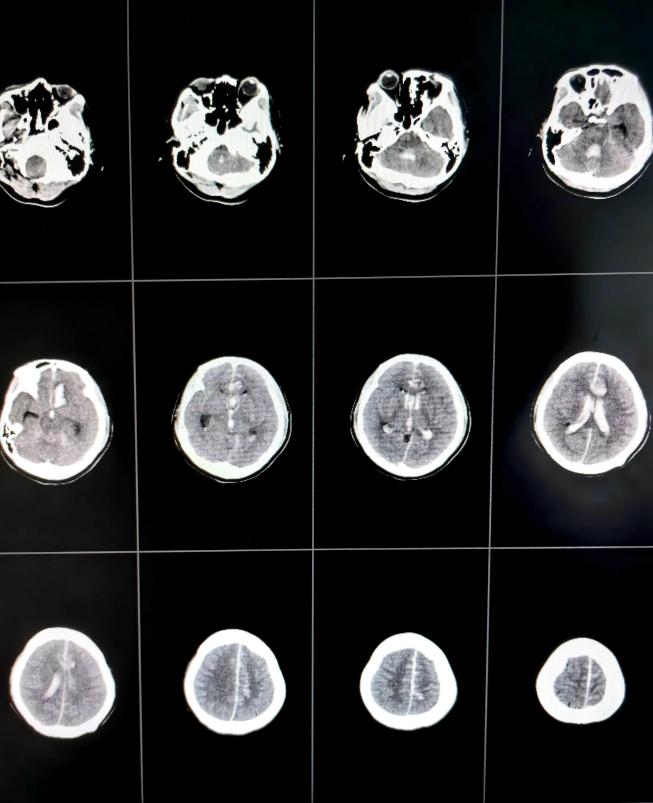

36岁的患者马女士(化名)因“突发意识不清3小时”从临近县医院转入我院,外院CT示蛛网膜下腔出血。来院时,马女士意识已陷入昏迷,频繁恶心呕吐,频发癫痫肢体抽搐。马女士进入急诊医学科后,脑科医院院长纪文军主任医师立即指示开通绿色通道,急诊复查头颅CT示左侧额叶脑出血、脑室积血、蛛网膜下腔出血;脑干受压、密度减低。相比于第一次CT出血明显增多,考虑为颅内动脉瘤二次破裂所致。

术前头颅CT提示颅内血肿、脑室积血、蛛网膜下腔出血